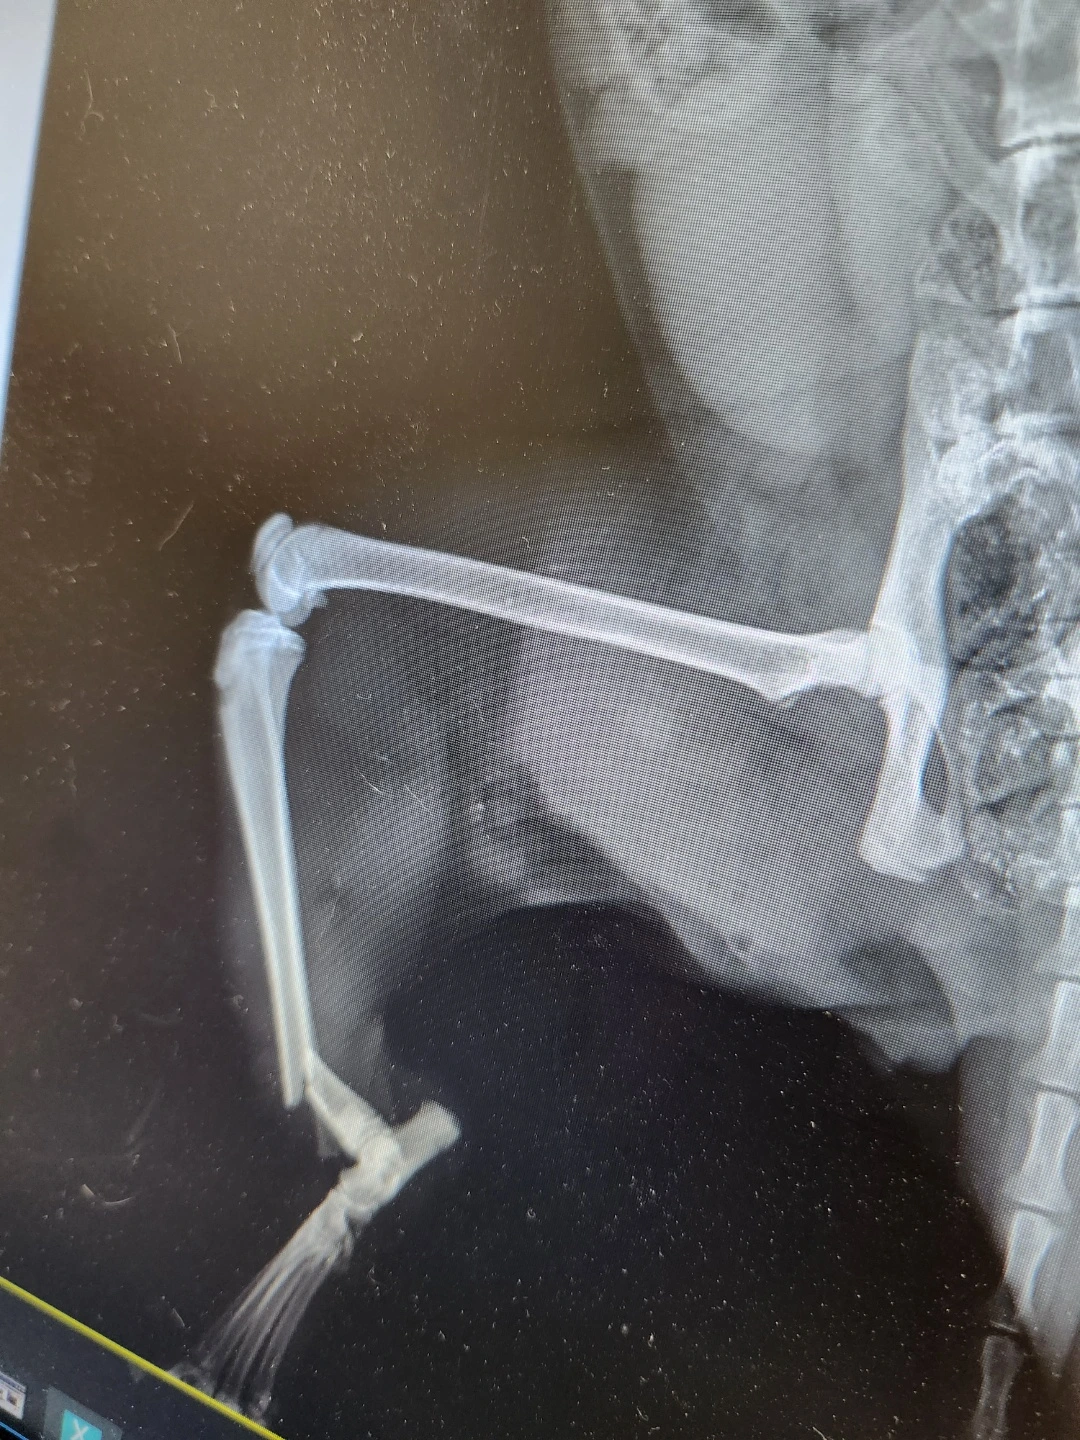

뒷다리가 골절되고 찢어진 상처부위로

감염이 심해서 한달 또는 두달이나

입원치료를 받아야 한다고해요